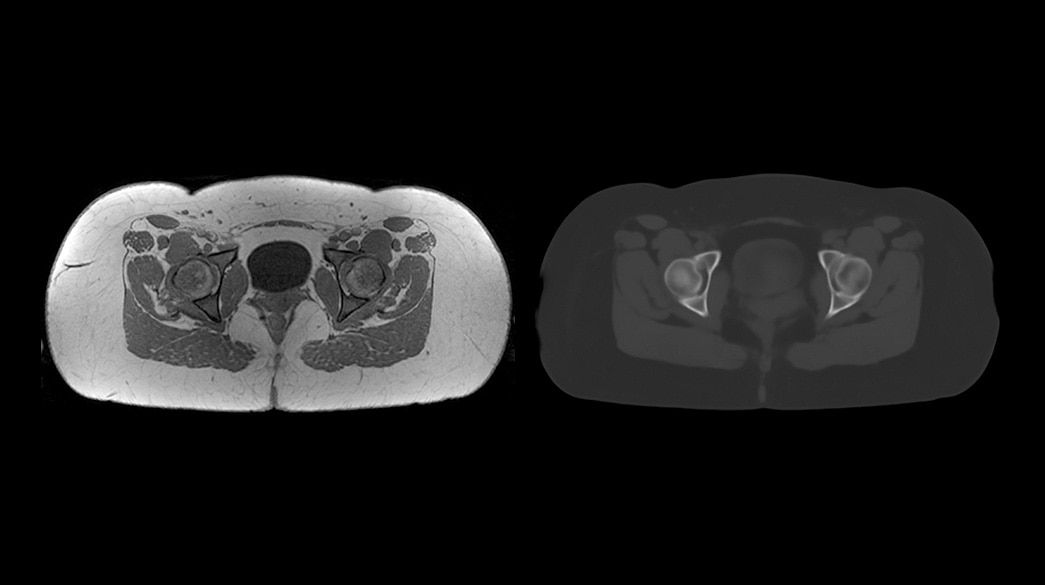

Consistent

Motion and distortion-reduced scans with high-resolution and contrast